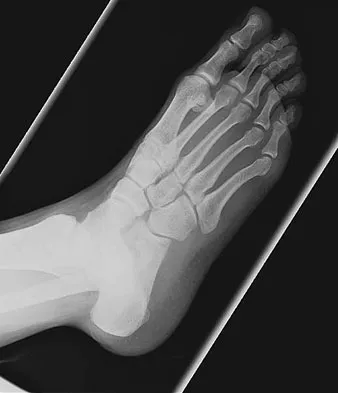

Figures 48a and 48b show the radiographs of a 26-year-old woman who fell down two steps and twisted her foot and ankle. What is the most appropriate treatment for this injury?

The patient has a zone 1 base of the fifth metatarsal fracture (Pseudojones) that represents a less serious injury compared to zone 2 and 3 fractures with regard to healing potential. Treatment is symptomatic and casting is not necessary. These fractures are well treated with a hard-soled shoe for comfort and weight bearing as tolerated. Surgical intervention is not warranted. Vorlat P, Achtergael W, Haentjens P: Predictors of outcome of non-displaced fractures of the base of the fifth metatarsal. Int Orthop 2007;31:5-10. Wiener BD, Linder JF, Giattini JF: Treatment of fractures of the fifth metatarsal: A prospective study. Foot Ankle Int 1997;18:267-269.